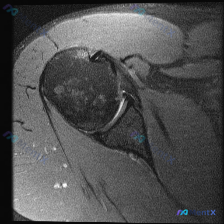

整理了一份肩部MRI病例讨论材料,医生的核心问题是排查盂唇病变,但看影像发现了一些矛盾点。先放MRI T2序列冠状位的分析: 1. 骨性结构:肱骨头、肩峰及锁骨远端轮廓尚可,未见骨折线或骨髓水肿 2. 肌腱与肩袖:冈上肌腱在肱骨大结节止点处形态异常,连续性中断,T2高信号 3. 关节与滑囊:肩峰下-...

最近整理了一份肩部MRI的病例讨论材料,患者主要问题是肩部疼痛,但问题明确指向"盂唇病变"范畴。先看T2冠状位图像的关键发现: 1. 冈上肌腱在肱骨大结节止点处有显著高信号,连续性可能中断 2. 肩峰下-三角肌下滑囊有明显的高信号积液 3. 关节盂唇区域信号存在改变 大家觉得这个病例更符合哪种诊断?...

整理了一个肩关节MRI-T2序列冠状位的病例讨论材料,医生提问关注盂唇病变,但影像最突出的是冈上肌腱全层撕裂。这份病例的核心疑问点和影像发现存在一定不匹配,大家第一眼怎么看?

看到一个肩部MRI(冠状位)的病例资料,用户最初的问题是关于「盂唇病理」,但整理的分析报告里有几个点挺值得讨论的: 先放影像的关键发现: - 冈上肌腱连续性中断,断端回缩,伴冈上肌肌腹萎缩、脂肪浸润 - 肩峰下-三角肌下滑囊积液,肩峰下间隙变窄,肱骨头上移 - 肱骨头大结节下方骨髓水肿 - 盂唇形态...